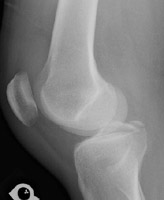

- Click on the image for a larger versionCLateral radiograph of the knee. This confirms the fracture at the location of the tibial spine.